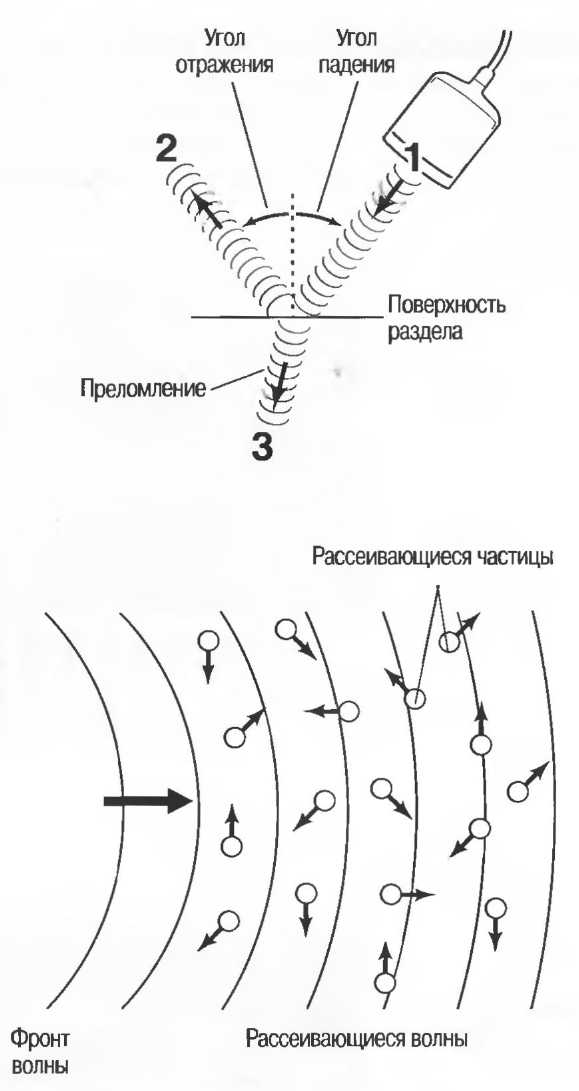

Часть излучаемых (1) волн отражается (2), при этом угол отражения равен углу падения. Другая часть волн (3) проходит через поверхность и преломляется, распространяясь далее под углом, отличным от угла падения. Чем более выражена разность акустического сопротивления двух сред, тем больше отражается ультразвук. Чем больше отношение скоростей распространения, тем больше преломление. Для практики важно знать, что при нулевом значении угла падения ультразвук падает на поверхность перпендикулярно.

Череп плода, дифрагма, стенки сосудов, соединительная ткань являются примерами зеркальных отражателей (рис. 6).

Ультразвуковые волны рассеиваются, когда размер отражающей структуры (рассеивателей) меньше, чем длина ультразвуковой волны. Только очень незначительная часть рассеянных сигналов возвращается назад в исходном направлении.

Печень и почечная паренхима являются примером рассеивающей среды.

Рис.6. Сагиттальный срез печени: имеется очень сильное (зеркальное) отражение от диафрагмы, являющейся таким мощным отражателем, что изображение печени повторяется за ней. Ультразвуковые волны проходят через печень после излучения, затем повторно — после отражения от диафрагмы, затем — от поверхностей тканевых структур.